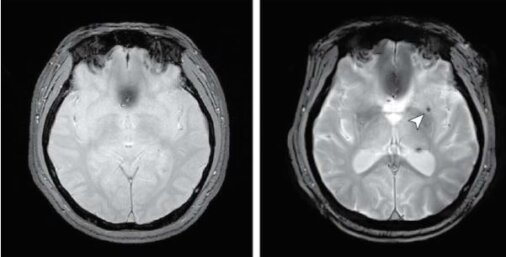

Οι εγκεφαλικές μικροαιμορραγίες αναγνωρίστηκαν ως εστιακές περιοχές μικρότερες από 10 mm με πολύ χαμηλό σήμα, όπως βαθμολογήθηκαν από ακτινολόγο που δεν γνώριζε την κατάσταση της άπνοιας ύπνου.

Εικόνες εγκεφαλικής μικροαιμορραγίας (CMB) κατά την έναρξη και την παρακολούθηση. Πίστωση: JAMA Network Open (2025). DOI: 10.1001/jamanetworkopen.2025.39874